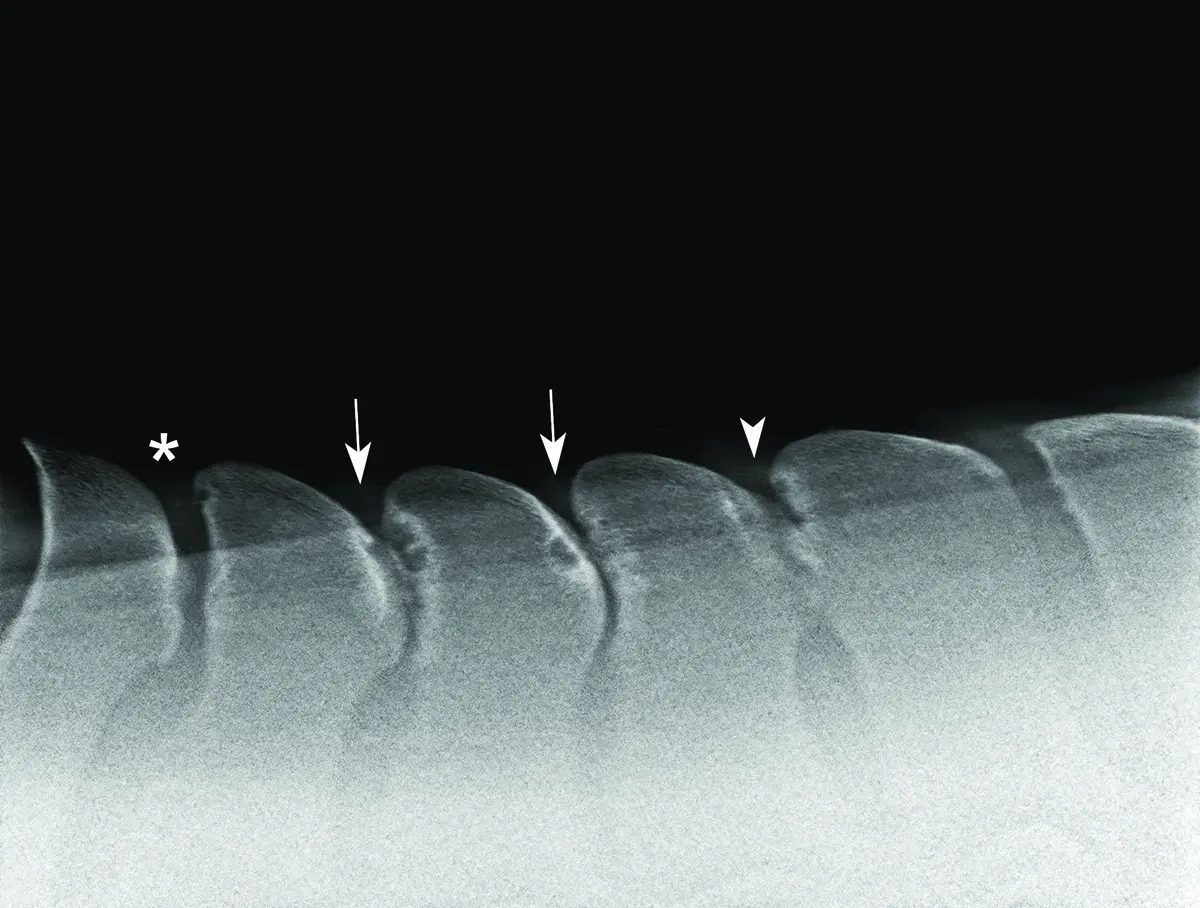

A horse with four sites of impingement with bone remodeling, suspected to be causing the horse’s pain under saddle. Photo by Alan Nixon

Post-operative image of the same horse following cranial wedge ostectomy of the four sites. Photo by Alan Nixon